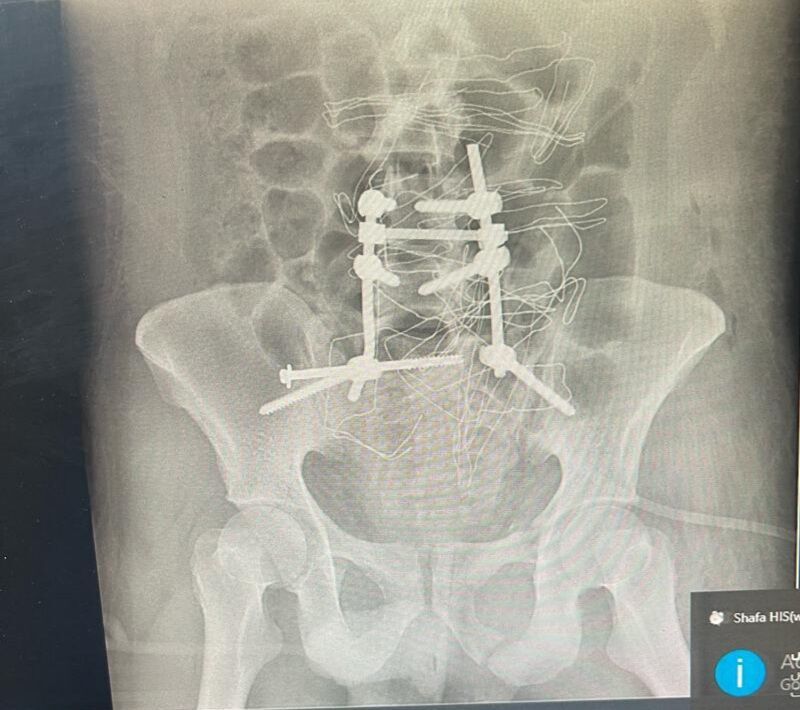

جراحی موفق اتصال مجدد ستون فقرات به لگن در پارس‌آباد

عمل جراحی پیچیده و سنگین اتصال مجدد ستون فقرات به لگن (Spinopelvic Fixation) با موفقیت در بیمارستان امام خمینی (ره) شهرستان پارس‌آباد انجام شد.

جراحی موفق اتصال مجدد ستون فقرات به لگن در پارس‌آبادبه گزارش عصرپرس، دکتر جعفر بشیری ، مدیر شبکه بهداشت و درمان پارس‌آباد گفت: این عمل سنگین با همکاری مشترک تیم جراحی متشکل از متخصصان ارتوپدی و جراحی مغز و اعصاب در بیمارستان امام خمینی (ره) پارس‌آباد با موفقیت انجام شد.

دکتر شهریار خوشبخت، متخصص جراحی ارتوپدی هم در تشریح روند درمان اظهار کرد: بیمار مردی ۲۵ ساله بود که در پی سقوط از ارتفاع دچار شکستگی شدید لگن و ستون فقرات و جداشدگی لگن شده بود.

وی افزود: بررسی‌های اولیه نشان‌دهنده هم‌گسیختگی کامل لگن و شکستگی استخوان ساکروم بود و بیمار توانایی حرکت دادن اندام‌های تحتانی خود را از دست داده بود.

این جراح ارتوپدی ادامه داد: عمل اتصال ستون فقرات به لگن از جمله جراحی‌های سنگین و پیشرفته ستون فقرات به شمار می‌رود که در موارد آسیب شدید ناحیه لگن انجام می‌شود تا نیروهای وارده از تنه به‌درستی از طریق لگن منتقل شده و امکان ترمیم استخوان‌ها فراهم شود.

دکتر کمالی‌فر متخصص جراحی مغز و اعصاب نیز گفت: بیمار تحت عمل جراحی وسیع و پیچیده قرار گرفت و با کارگذاری وسایل فیکس‌کننده در مهره‌های چهارم و پنجم کمری و اتصال مستقیم آن‌ها به استخوان لگن (ایلیوم)، با همکاری جراح و متخصص ارتوپدی پایداری ستون فقرات مجدداً برقرار شد.

وی با بیان اینکه این جراحی حدود چهار ساعت به طول انجامید، گفت: این عمل برای نخستین‌بار در شهرستان پارس‌آباد با همکاری جراح مغز و اعصاب انجام شد و خوشبختانه پس از جراحی، علایم عصبی بیمار برطرف و حال عمومی وی رضایت‌بخش است.